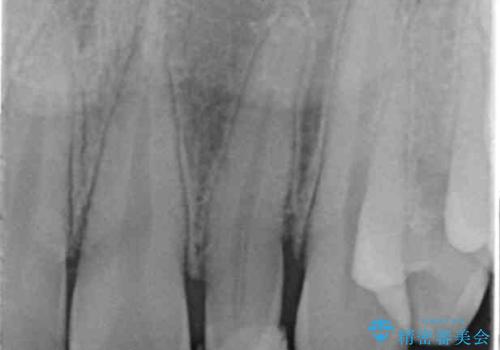

- 左上の前歯の変色が気になるとのことで来院されました。

もともと小さい歯(矮小歯)に樹脂が盛り足されている状態でした。

- 左上2:仮歯+ジルコニアクラウン/11,000円+110,000円費用は治療当時の料金となります